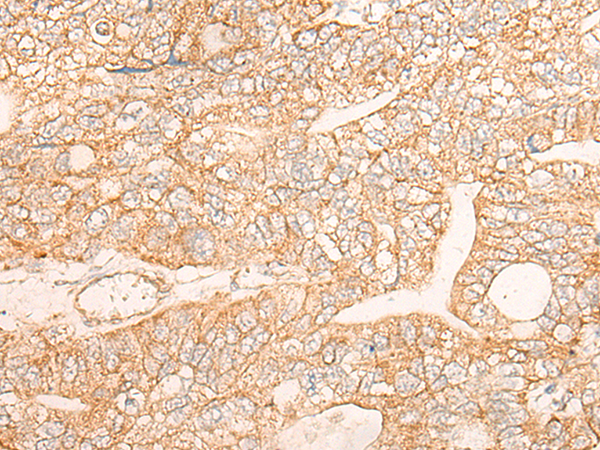

IHC positive control: |

Human liver cancer and Human gastric cancer |

IHC Recommend dilution: |

30-150 |